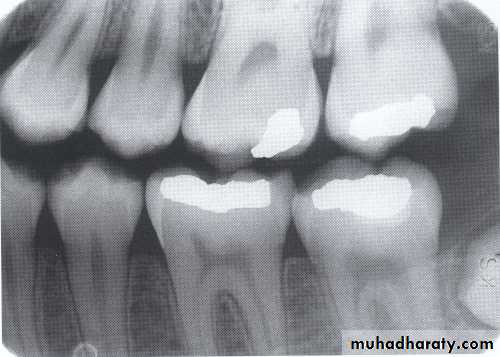

The bitewing radiograph is the view of choice for the evaluation of periodontal disease.

• Radiographically; the defective filling identified with open or loose contacts, poor contour, uneven marginal ridges over-hangs.

Detection of Periodontal Disease

caries

Overhang rest.